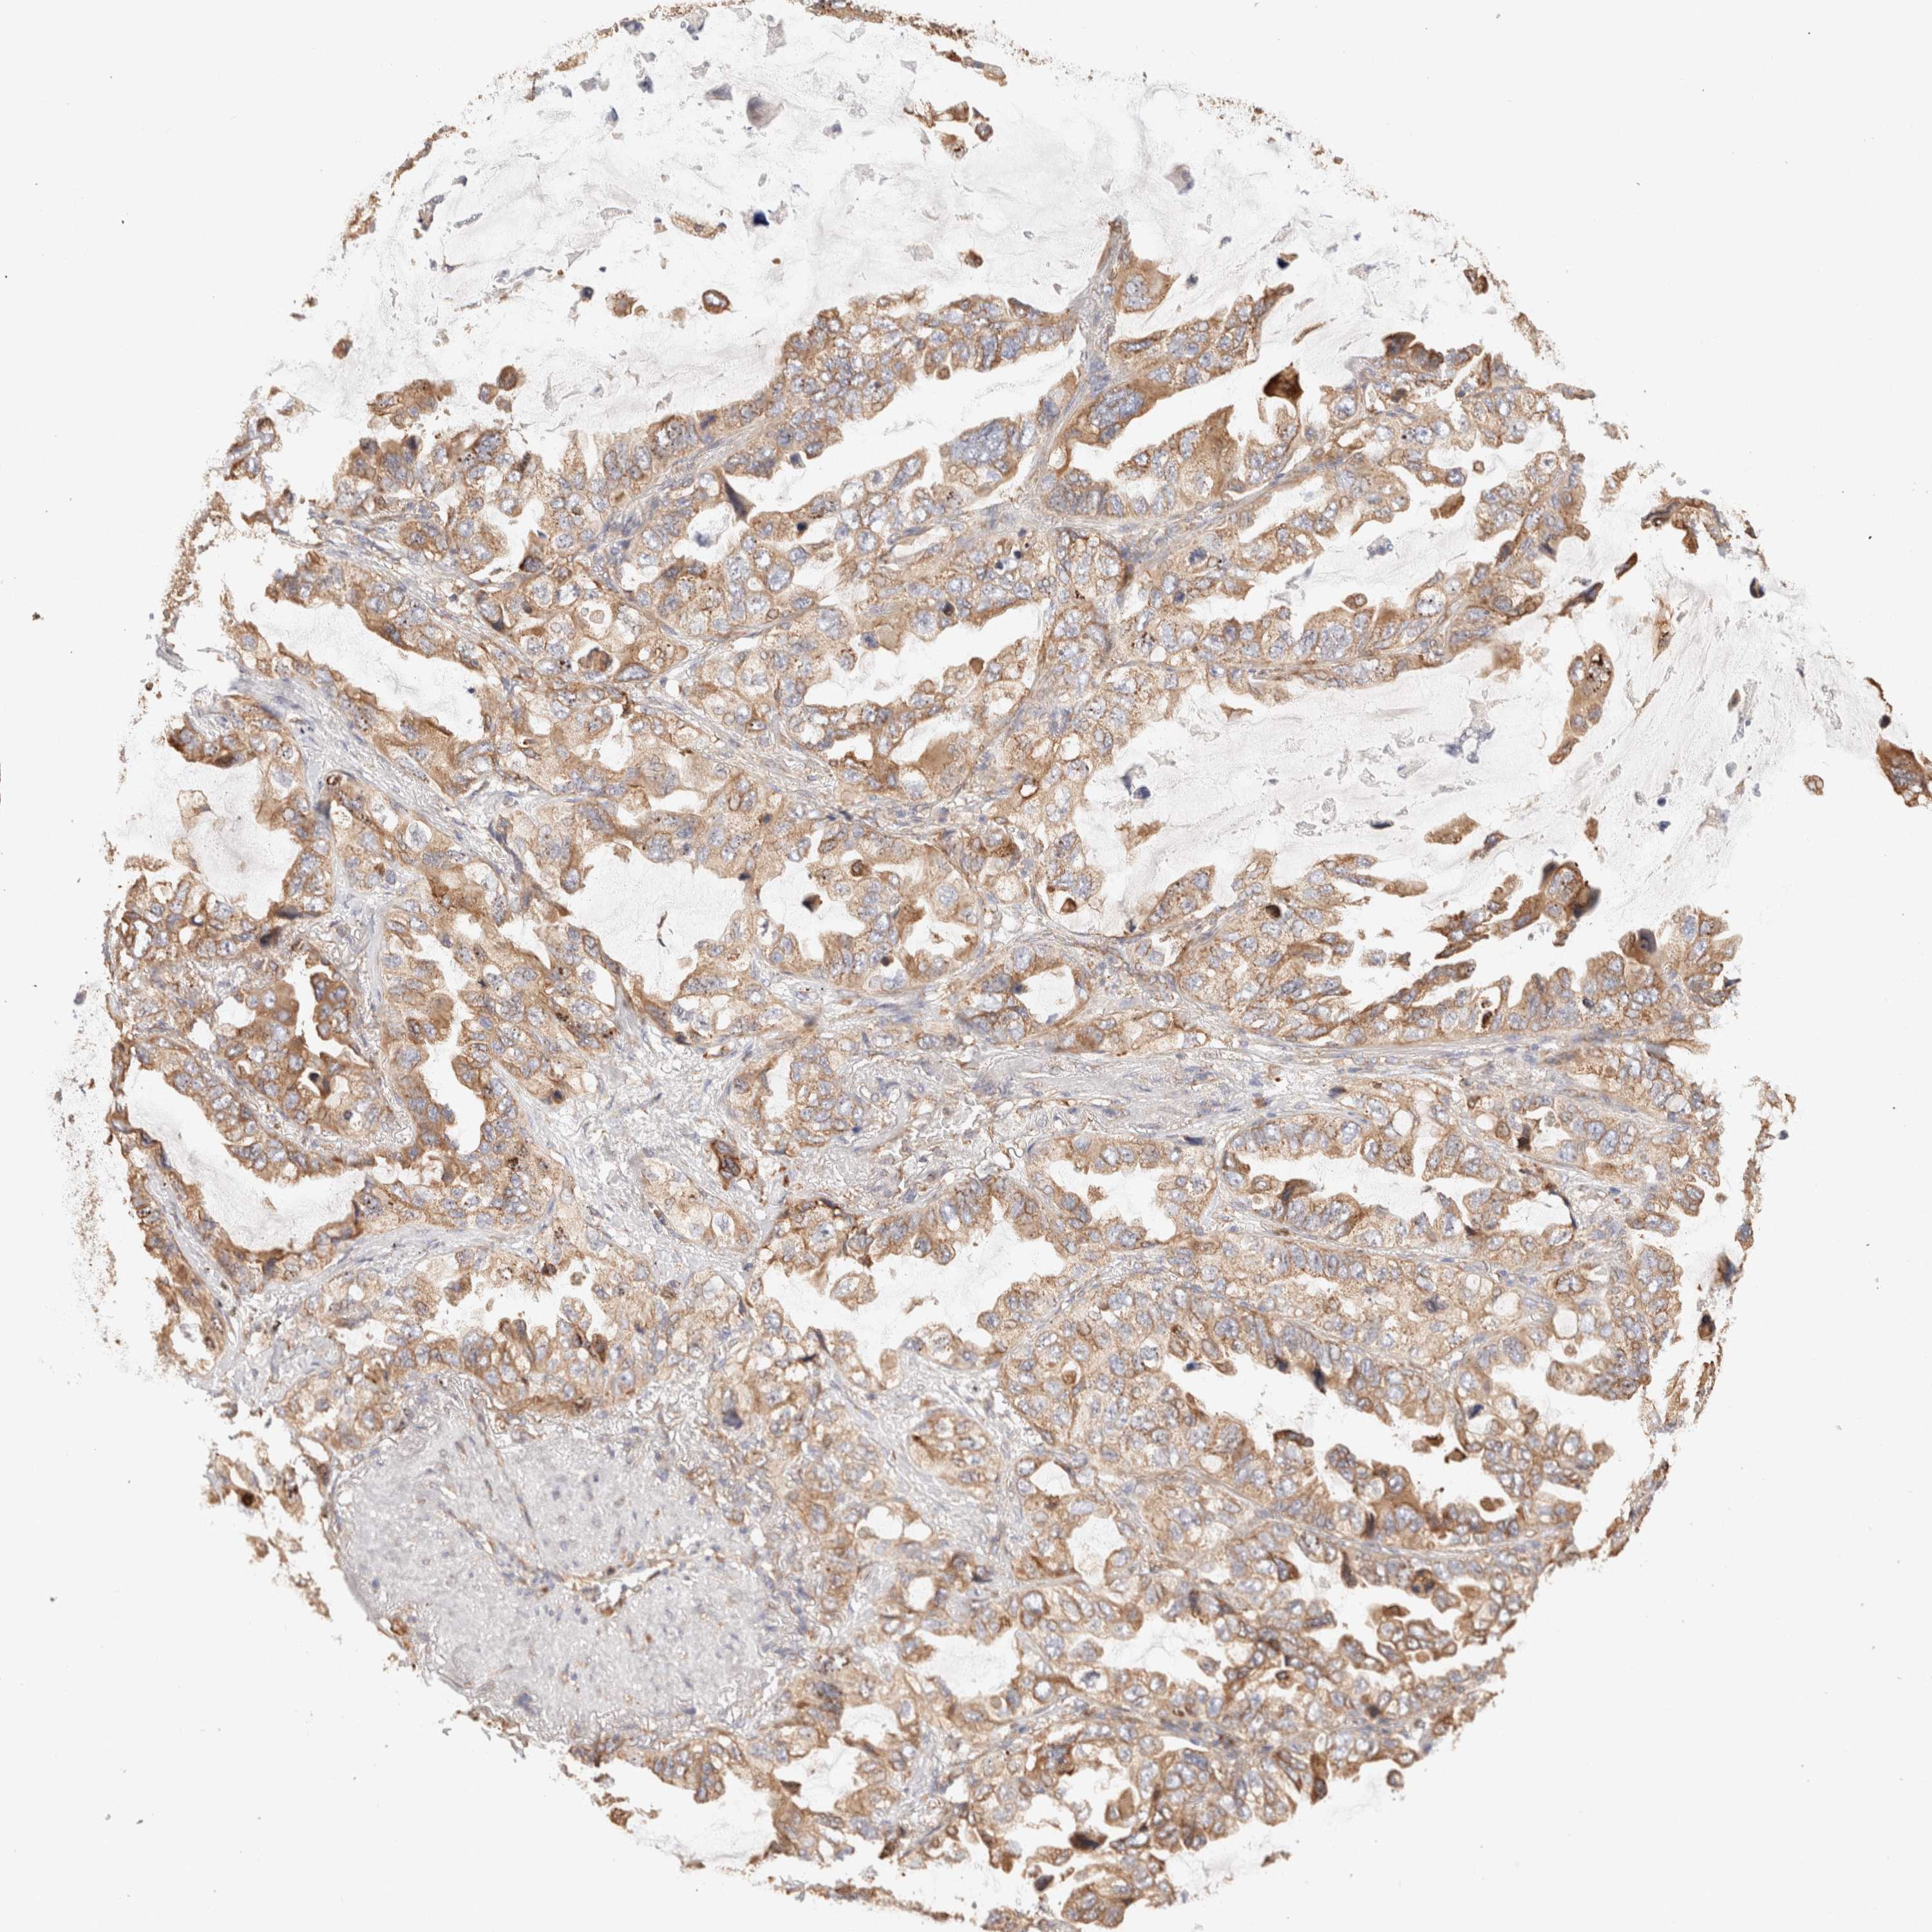

CANCER LUNG CANCER Show tissue menu

LUAD TCGA LUAD VALIDATION LUSC TCGA LUSC VALIDATION PROTEIN LUAD CPTAC PROTEIN LUSC CPTAC PROTEIN EXPRESSION

ANTIBODIES

AND

VALIDATION